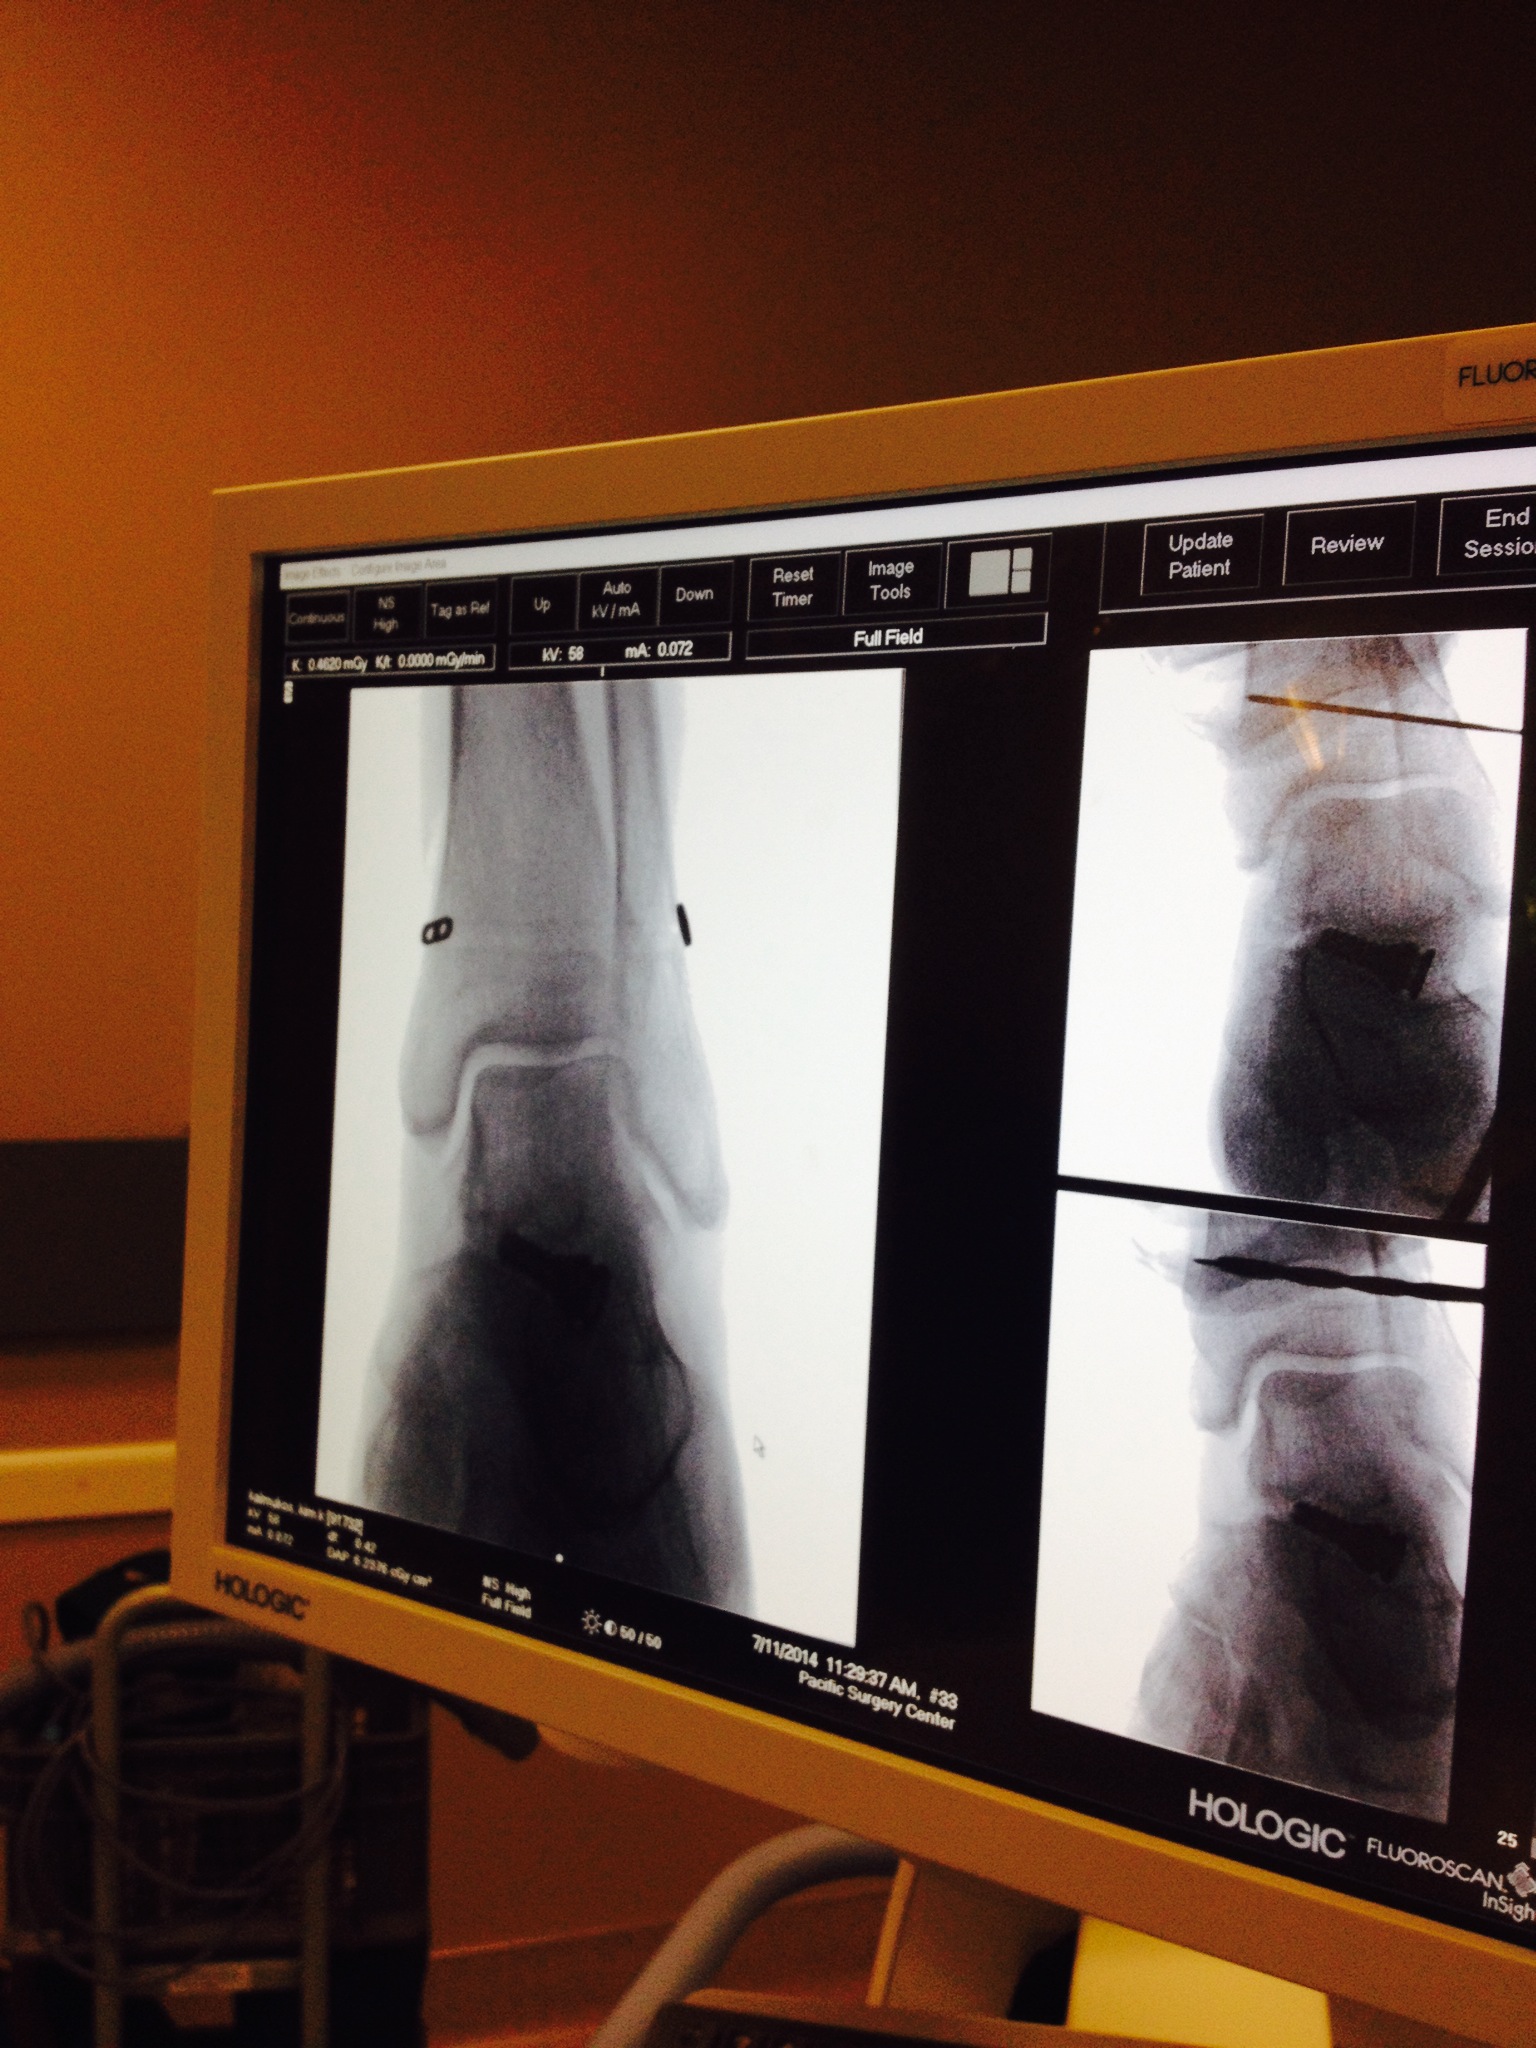

Here are photos (click on the photos to enlarge) taken during the Arthrex TightRope Dynamic Stabilization Surgery. I consider this surgery to be very minimally invasive. Only a couple of stitches in my lateral ankle/fibula bone. I was just a little over an hour and my husband was able to see me in recovery. I woke up as usual with no complications and I began my usual hunger spree of “Feed Me”. I did remember saying, “Why do I have to wake up, I don’t want too because I really didn’t want to face the reality of life in a non weight bearing status again.” For me surgery has always been the easy part. Life afterwards is the struggle.